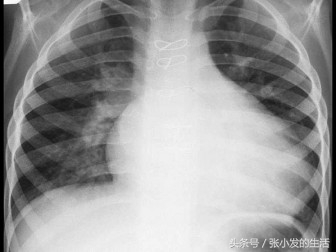

A.原发性(特发性)中枢性尿崩症

51[单选题]女孩11岁,胸骨左缘第2肋间听到Ⅱ级收缩期杂音,肺动脉瓣区第二心音固定分裂。胸片示如图,右房右室增大。心电图为不完全右束支阻滞,最可能的诊断是 ( )

A.房间隔缺损

B.室间隔缺损

C.肺动脉狭窄

D.法洛四联症

E.动脉导管未闭

正确答案:A